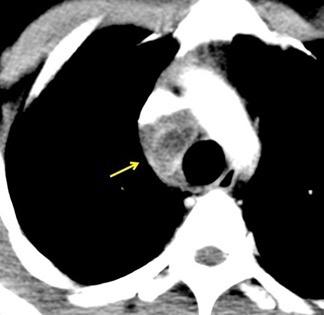

109. LIPOMA INTRACAVA

Edad: 40-50 años

3% segregan catecolaminas.

(En el área Paravertebral +/-50%.)

Intenso realce con el contraste.

32 años .Preeclampsia a los 19. Hipertensión no controlada. Masa paravertebral sólida que se realza intensamente con afectación ósea.

Yue Y t al. Asymptomatic left posterior mediastinal functional Paraganglioma. A case report. Medicine . 2019